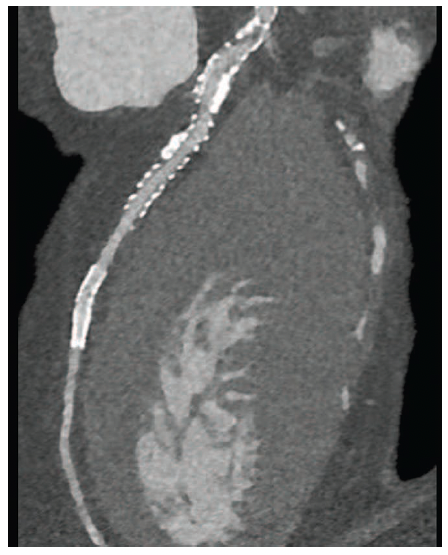

reformat (CPR).

The high level of spatial resolution in a diagnostic cardiac computed tomography angiography (CCTA) scan conducted using photon-counting CT can help clinicians determine whether a patient with cardiac disease also requires an invasive coronary angiography procedure. In this case, a 5’6”, 180 lb male patient with coronary artery disease was scanned on a photon-counting CT scanner (the NAEOTOM Alpha, Siemens Healthineers) for follow-up care after stenting and evaluation for in-stent restenosis. The CT scan, which used a sequential Quantum HD Cardiac CCTA acquisition and was reconstructed in the Best Diastolic phase utilizing a 1024x1024 matrix, was performed at 140 kVp with an estimated patient radiation dose of 4 mSv. The scan revealed not only multiple areas of in-stent restenosis (Figures 1-2), but also soft and hard plaque in non-stented areas (Figures 1-3).